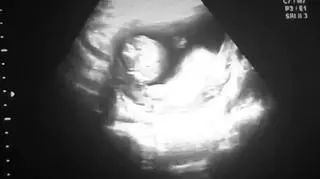

W reportażu TVN24 "Miała mieć na imię..." opowiedziana została historia pani Mariny, która w 17. tygodniu ciąży usłyszała od lekarza, że z jej dzieckiem wszystko jest w porządku, a w 30. tygodniu - już od innego specjalisty - że jej dziecko cierpi na bezczaszkowie. Kobieta uzyskała opinię, że ciąża zagraża jej życiu i zdrowiu, a następnie zgłosiła się z nią do szpitala przy Inflanckiej w Warszawie chcąc dokonać aborcji. Tam jednak usłyszała odmowę. Sytuacja zmieniła się, kiedy z urlopu wrócił dyrektor placówki, ginekolog profesor Łukasz Wicherek. Zmienił decyzję podwładnych i zdecydował o terminacji ciąży. W 33. tygodniu u pani Mariny wywołano poród. Dziecko urodziło się martwe.